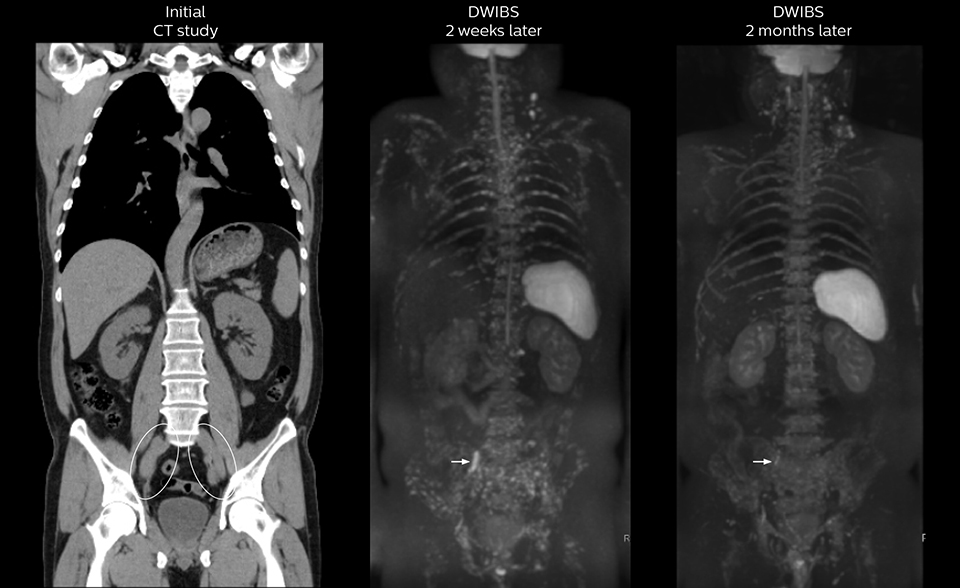

Active education of referring physicians helped increase referrals

After implementing the improved whole body protocol, the radiology team initially did not see a large increase in referrals, although Dr. Nobusawa saw clinical cases where the DWIBS images provided him valuable information for diagnosis. This is why Dr. Nobusawa and Mr. Naka started to actively educate referring physicians about the value of whole body DWIBS. They organized several presentations for physicians in the hospital, where they explained how DWIBS can be of value in oncology patients. The information it provides can be useful for physicians when staging cancer, as well as when determining or adjusting treatment strategy.

As oncologists and surgeons have learned more about DWIBS, referrals for the exams have increased. In 2015, the 326-bed hospital’s radiology department doubled their number of whole body DWIBS exams compared to 2014.

Mr. Naka remembers some cases where DWIBS provided remarkable information. “In one example, DWIBS visualized bone lesions that could not be seen on PET or SPECT. In another case we had found a bone lesion when a normal L-spine scan for narrowing of the disk space was done. One extra DWIBS scan (2 stations, 8 minutes) demonstrated a lesion that later was confirmed to be the primary region of cancer.”